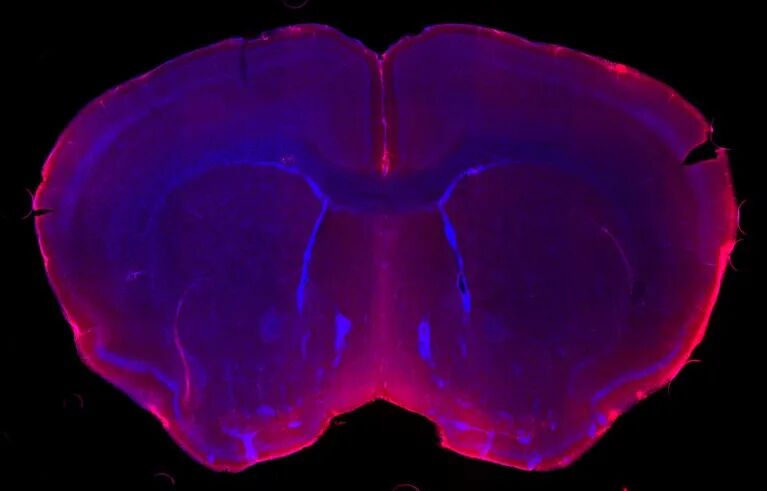

这种态度的转变在研究者群体中很普遍,Leonardo Tonelli说。他是美国国家心理健康研究所神经内分泌和神经免疫学项目主任。以他的经验,几乎每一个为所里审查基金申请的神经学家都接受这种联系,尽管许多人仍然需要跟上神经免疫学的最新发现,这些发现已经开始揭示潜在的机制。加州斯坦福大学的神经免疫学家Tony Wyss-Coray说,人们急于了解大脑和免疫系统是如何结合在一起的,提出了大量问题。“这对正常的大脑功能或疾病有多重要?这是一个很难回答的问题。”二十多年前,神经免疫学家Michal Schwartz刚刚在以色列雷霍沃特的魏茨曼科学研究所建立她的实验室时,她老忍不住问自己一个不受欢迎的问题:大脑真的完全切断了免疫保护吗? “人们曾经普遍认为,大脑不能承受任何免疫活动。人人都以为如果有任何免疫激活,这是个病变的迹象。”她说。“但像大脑这样极其重要的组织,竟不能受益于免疫系统的协助,这是说不通的。”大脑是免疫系统禁区的想法在几十年前就生根了。在20世纪20年代,日本科学家Y. Shirai报告[1]说,当肿瘤细胞被植入老鼠体内时,免疫反应会破坏它们,但当它们被植入大脑时,它们却存活了下来——这表明免疫反应微弱或缺乏。20世纪40年代也有类似的发现。大多数科学家还认为,大脑缺乏一个运输免疫分子进出的系统——即存在于身体其他部位的淋巴引流系统——尽管脑的此类系统在两个多世纪前已首次得到了描述[2]。当时流行的观点是,大脑和免疫系统在很大程度上是分开的。人们认为这两者只有在不利的环境下才会出现相互作用:当免疫细胞失控,攻击自体细胞时,如多发性硬化症。因此,在20世纪90年代末,Schwartz和她的团队报导[3]中枢神经系统急性损伤后,两种类型的免疫细胞——巨噬细胞和T细胞——保护神经元免受损伤,并支持它们的恢复,许多科学家对此表示怀疑。回忆起来,Schwartz说,“每个人都告诉我,你错得彻底。”自那些早期实验以来,Schwartz的团队和其他人已经积累了大量的证据,表明即使没有自身免疫性疾病,免疫细胞也确实在大脑中扮演着重要的角色。例如,研究人员表明,在免疫系统缺陷基因改造小鼠身上,神经退行性疾病,如运动神经元疾病(肌萎缩性侧索硬化症)和阿尔茨海默病似乎进展得更快[4],而恢复免疫系统则减缓了它们的进展。科学家还揭示了小胶质细胞在阿尔茨海默病中的潜在作用。图3. 脑脊液(红色)通过流经大脑保护层的血管中的微小缝隙渗入脑组织(蓝色)。图片来源:Antoine Drieu, Kipnis lab, Washington University in St. Louis最近,科学家们已经证明,大脑边缘的免疫细胞在神经退行性疾病中很活跃。在检查了阿尔茨海默病患者的脑脊液后,Wyss-Coray及同事发现了证据,表明大脑充满液体的边界中T细胞数量增加[5]。Wyss-Coray说,这些免疫细胞数量的增加表明它们可能在这种疾病中有所作用。但是,免疫细胞究竟是对大脑有害还是有益,还是一个有待解决的问题。在对阿尔茨海默病和其他神经退行性疾病的研究中,Wyss-Coray及同事提出,免疫系统可能通过释放促进炎症因子和触发细胞死亡而破坏神经元。另一些人则认为T细胞和其他免疫细胞可以起到保护作用。例如,Schwartz的研究小组报告说[6],在阿尔茨海默病的小鼠模型中,增强免疫反应可以清除淀粉样斑块(该疾病的病理特征),并提高认知能力。